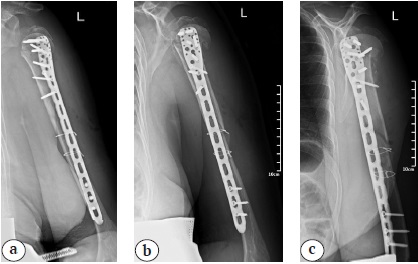

After patient examenation and preparing for surgical treatment open direct repositioning and plate osteosynthesis were performed through the deltoid-pectoral approach with an additional lateral approach. Surgical treatment was performed in the beach-chair position.

The first step was passing the lag screws through the diaphyseal part of the fracture; however, satisfactory repositioning was not achieved. The lag screws were removed and two cerclage sutures were applied (Fig. 2). Then osteosynthesis was performed with a long PHILOS plate (Synthes) (Fig. 3).

Fig. 2. Intraoperative X-rays: a — humerus diaphysis fragments displacement; b — reposition of the humerus shaft, lag screws insertion; c — loss of reposition; d — removal of lag screws, cerclages ostheosynthesis

Fig. 3. Postoperative X-ray’s after osteosynthesis of the humerus with a PHILOS Long plate and cerclages: a — frontal view; b — lateral view; c — oblique view

Postoperatively, the patient retained paresis of the radial nerve, and therapy with special neurological therapy was started. Additionally, immobilization in a shoulder brace was performed for 6 weeks, followed by active rehabilitation therapy and staged radiography. Radial nerve paresis resolved 9 months postoperatively with complete radial nerve function restoration.